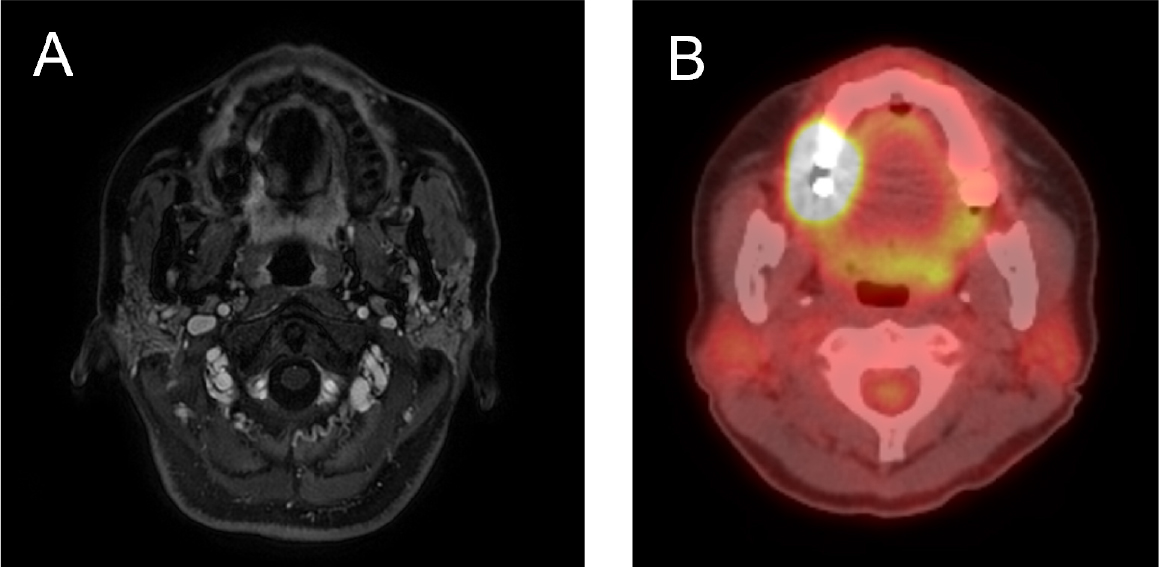

Computed tomography (CT), magnetic resonance imaging (MRI), and 18F-fluorodeoxyglucose (FDG) positron emission tomography (PET) were performed for further assessments. The MRI showed an infiltrative enhancing lesion in the right hard palate and gingival area. The PET/CT showed increased FDG uptake involving the right hard palate and adjacent gingiva. No abnormal increase in FDG uptake was observed, thereby suggesting lymph node or distant metastases (Fig. 2). Based on the above results, partial maxillectomy involving the right side of the maxilla and supraomohyoid neck dissection on the right side were planned. Additionally, reconstruction using a scapular free flap was planned to promote dental implant placement while minimizing donor-site morbidity.

Fig. 2.

(A) Axial view of magnetic resonance image showing enhancing lesions in the right hard palate and gingival area, (B) Axial view of a PET-CT scan showing increased FDG uptake involving the right hard palate and adjacent gingiva. FDG, fluorodeoxyglucose; PET-CT, positron emission tomography- computed tomography.